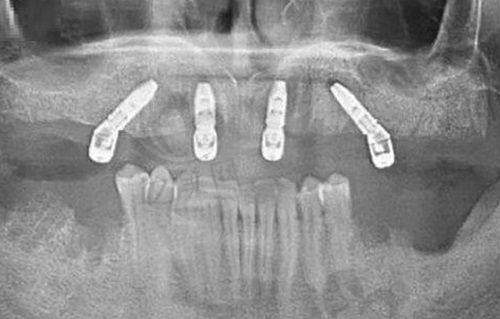

即刻种植技术:All - on - 4半口种植可实现当天咀嚼。

沈阳国睿口腔门诊部实例

以下是一些患者实例:

患者A是一位种植牙患者,选择了德国种植体,使用5年后种植体无松动,对该门诊部的种植牙技术和性价比非常满意。